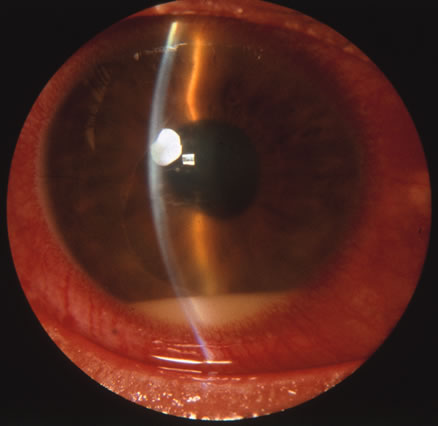

In primary ocular HSV infections, a severe follicular conjunctivitis with regional adenopathy is present. Vesicles may appear on the eyelid skin or lid margin, producing blepharitis (Fig. 3). Corneal involvement initially takes the form of a superficial punctate keratitis, which may progress to dendritic or geographic ulceration. Stromal infiltrates and uveitis are less common and relatively mild in primary disease. In uncomplicated cases, lesions usually heal completely in 2 to 3 weeks without scarring. Most cases of ocular HSV are recurrences. Recrudescent ocular herpes may take the form of dendritic or geographic ulcers, recurrent erosions, interstitial or disciform stromal keratitis, and anterior uveitis.3 HSV may also be an agent of retinitis and acute retinal necrosis (Fig. 4).